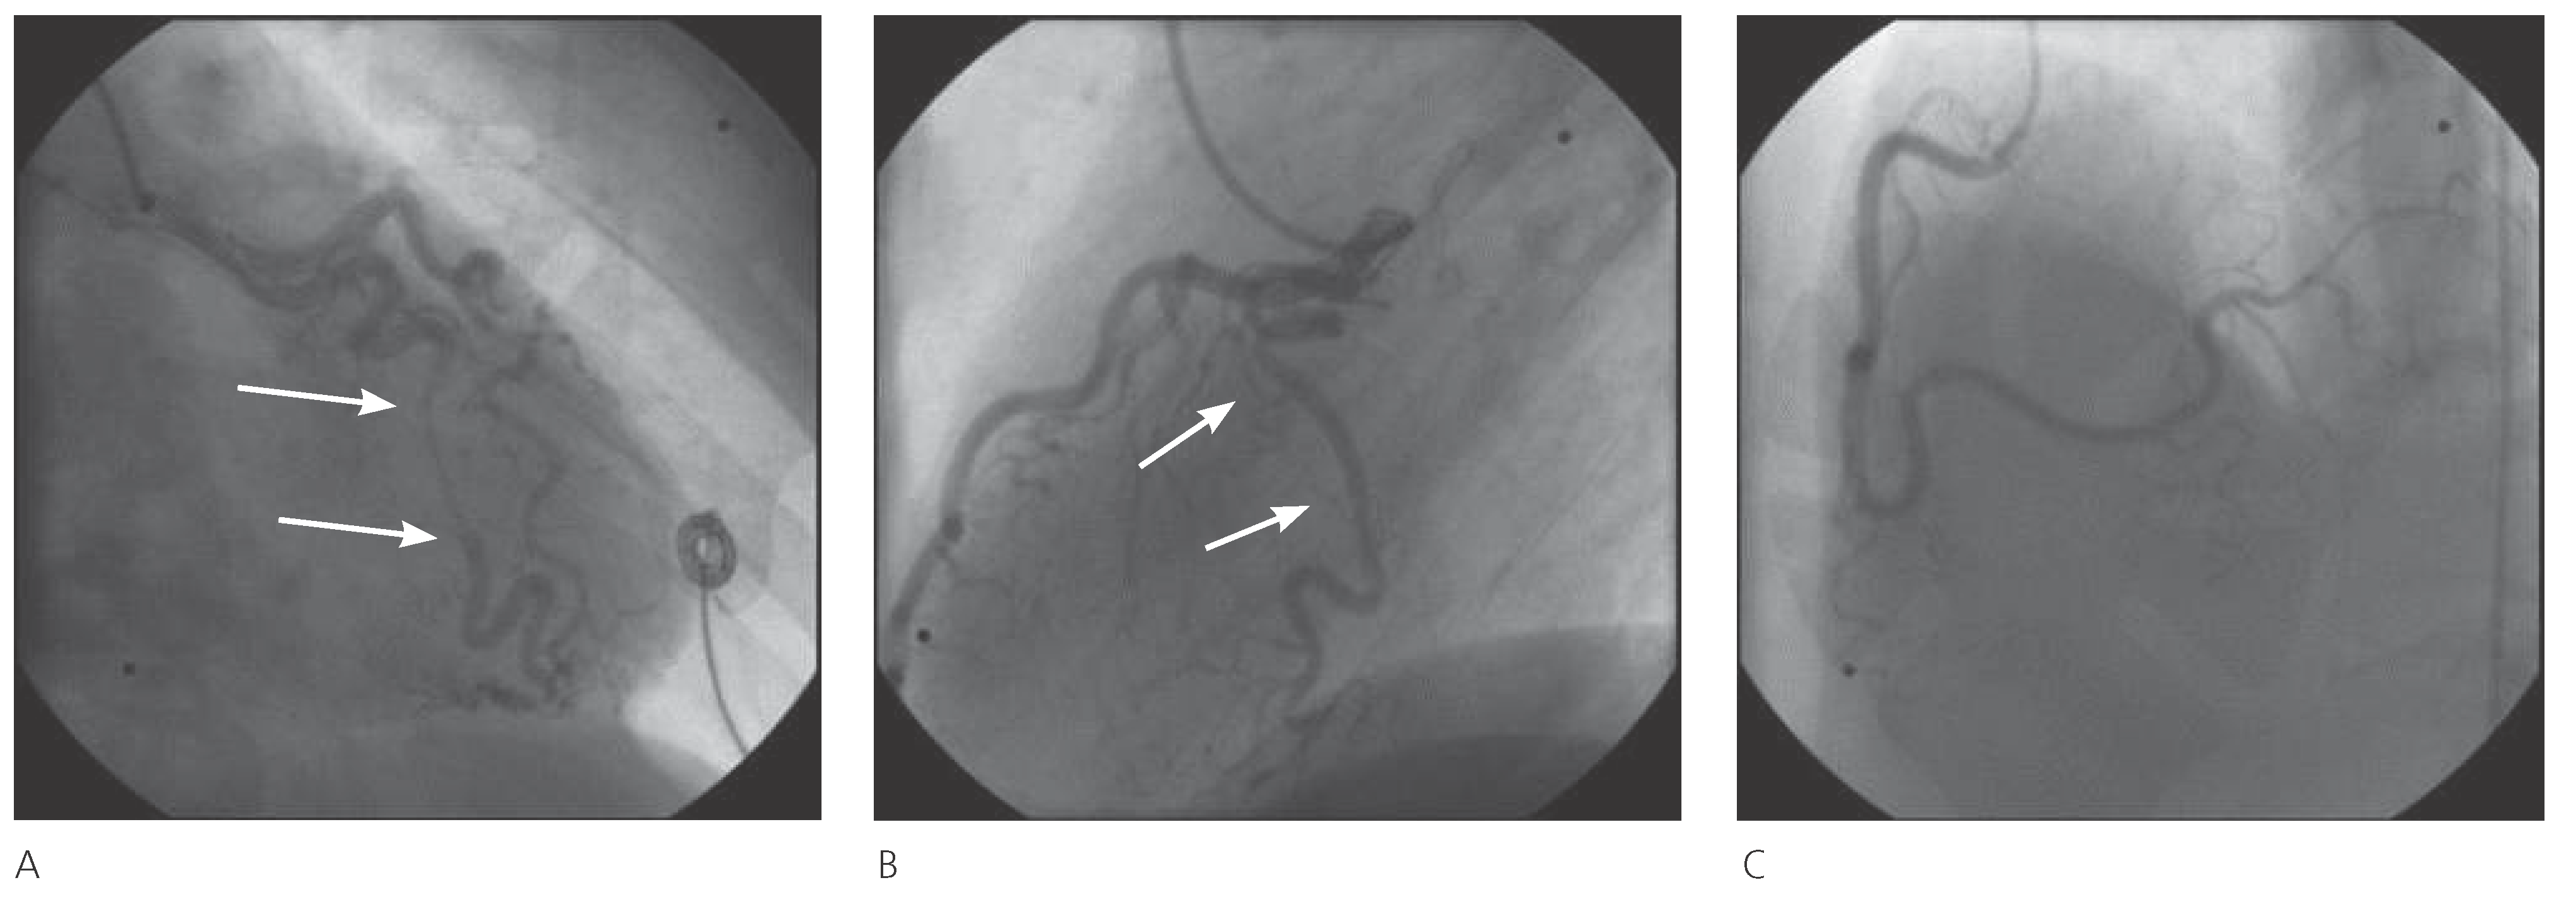

In November 2003, a 46-year-old woman, active smoker, with mild hypertension and a family history of cardiovascular disease, reported a sudden onset of pressurelike substernal chest pain, radiating to both arms: while being transported to the emergency department by ambulance, a cardiac arrest occurred with ventricular fibrillation as the first rhythm established. Cardiopulmonary resuscitation and direct current shock were performed and the return of spontaneous circulation was achieved. In the emergency department ECG showed regular sinus rhythm, 65 bpm, and ST depression in V2–V6 leads. The coronary angiography showed a long (around 25 mm) subtotal stenosis and narrowed vessel aspect (TIMI I) in the middle part of the tortuous LCx, with a small radiolucent defect in the proximal segment of the lesion, suggestive features of spontaneous dissection, without any other detectable coronary lesion. The patient underwent percutaneous coronary intervention (PCI) and three drug-eluting stents (Taxus-paclitaxel) were successfully implanted (Figure 1), resulting in restoration of TIMI III flow and resolution of symptoms. The patient improved and was discharged on double antiplatelet therapy for twelve months (Aspirin® and clopidogrel), beta-blocker and statin. Follow-up coronary angiography at three months demonstrated patency of the stents, without evidence of residual disease, and her medical treatment was confirmed. Thirty-four months later, in August 2006, the patient was admitted with unstable angina, positive troponin and T-wave inversion in precordial leads (V2–V5). The coronary angiography showed a fresh and long (>20 mm) dissection of the distal RCA propagating to the posterior lateral branch without any sign of disease in the other vessels (Figure 2). Once again the proximal segment of the lesion presented a tiny radiolucent line. In light of the unfavourable location of the lesion, its extension, the small size of the target vessel, and the symptoms easily managed with nitrates, a conservative treatment was deemed necessary. The patient had a favourable clinical course and discharge occurred three days later, on aspirin and clopidogrel for 3 months, beta-blocker and statin. In the follow-up the patient remained almost asymptomatic. Forty-eight months later, in Au gust 2010, because of recurrence of chest pain and inconclusive Echo-stress test, a new coronary angio graphy was performed. It showed a spontaneous recanalisation of the previously dissected RCA and posterior lateral branch, with a small persisting lesion (Figure 3); no sign of injury was found in the other vessels. Aspirin was confirmed at discharge. Since then, the patient is still on aspirin and beta-blocker, and completely asymptomatic at the follow-ups, last one performed in February 2014.

Figure 2. August 2006 coronary angiography. A. Normal LAD and normal LCx artery, with patency of the previous stents on middle LCx. B. Fresh, long dissection of distal RCA and posterior lateral branch (arrows).